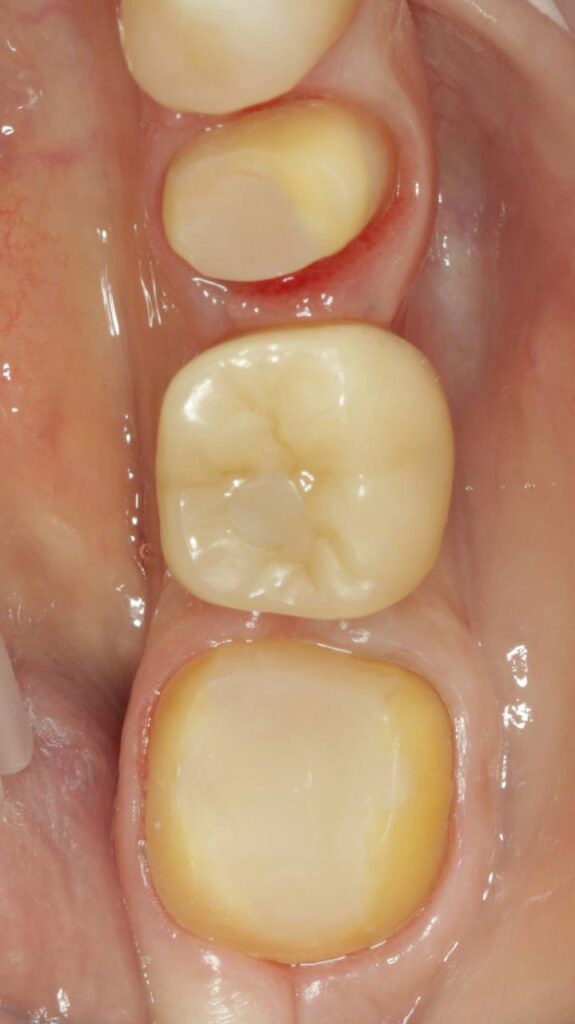

Протезирование коронками из диоксида циркония, после эндодонтического лечения — Исламов Л.А.(01.04.2026)